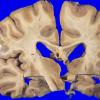

Neuronal Ceroid Lipofuscinosis (NCL) (8)